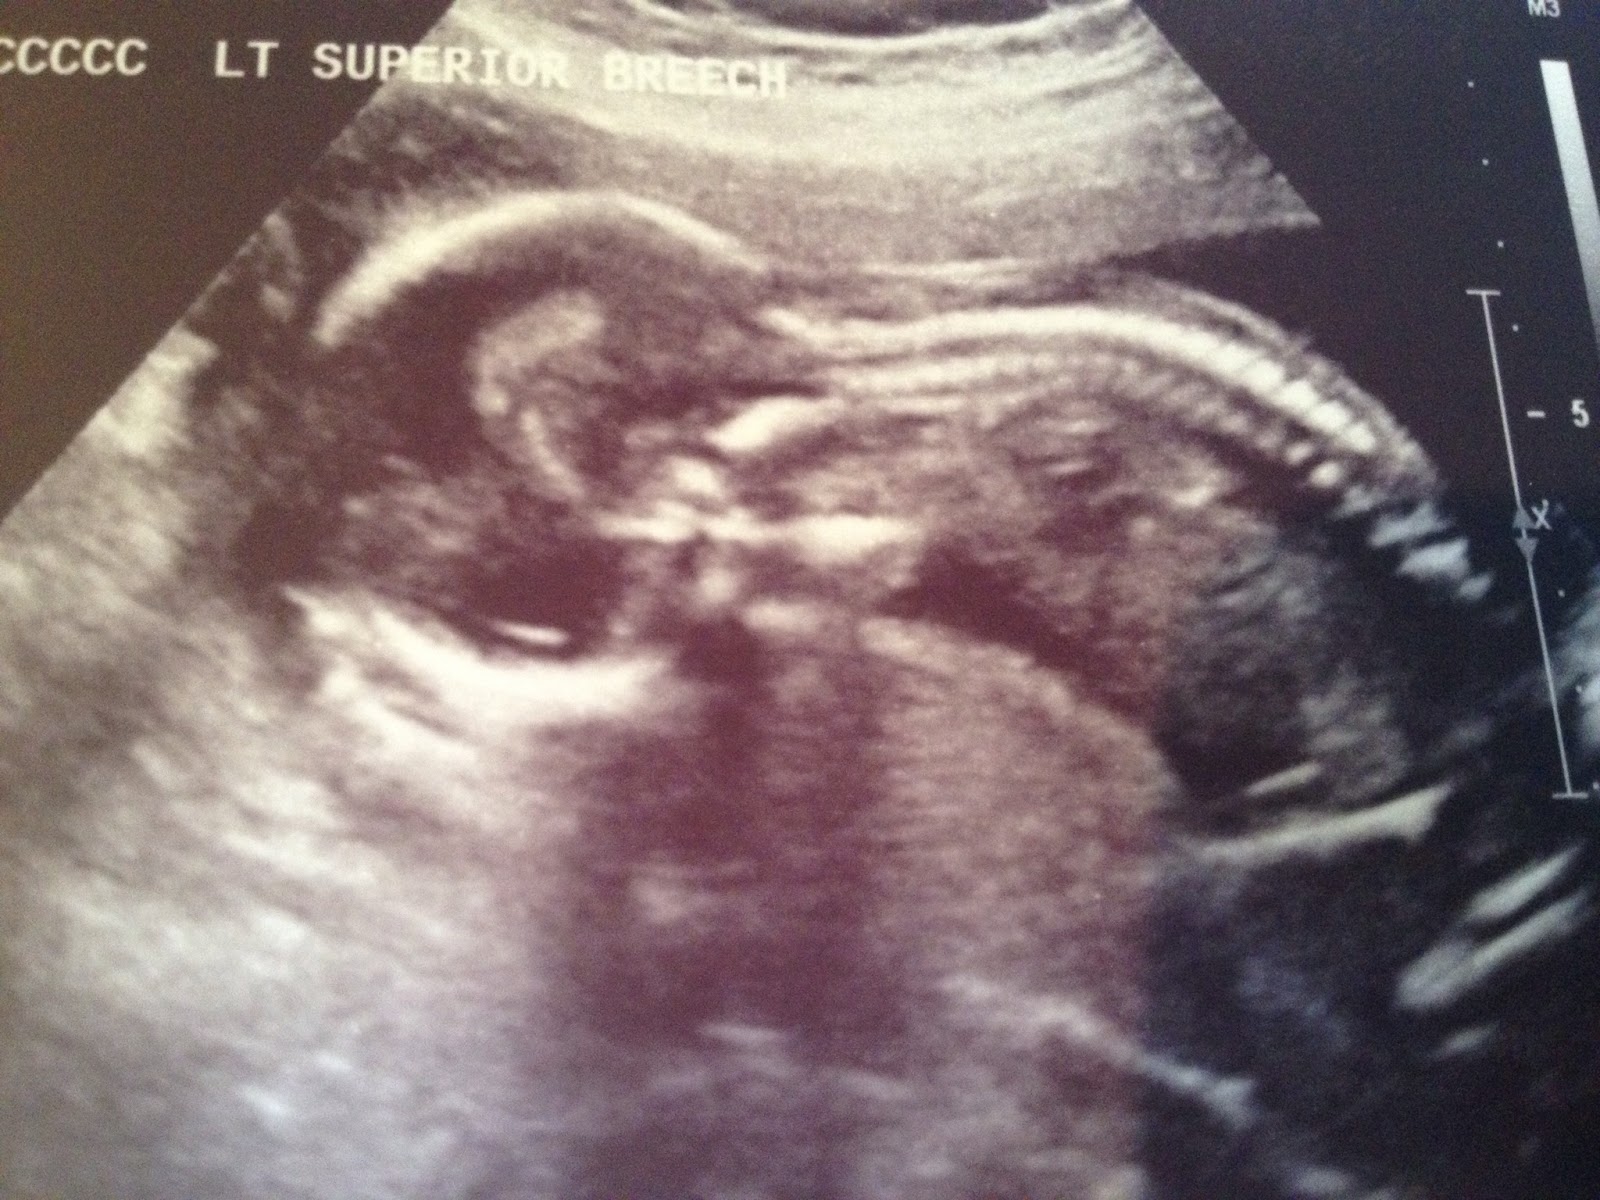

From burrustwins.weebly.com

18 Week Level 2 Ultrasound Our Journey to Twins Indications For Level 2 Ultrasound The indications for targeted (level ii) ultrasound include, but are not limited to: Suspected fetal anomaly during a level i examination severe. Level ii ultrasound:differential diagnosis of fetal structural abnormalities found on ultrasound. (detailed fetal anatomic survey, 76811)* previous fetus or child with a congenital, genetic, or chromosomal. What exactly does a 20 week anatomy scan show? Images are much. Indications For Level 2 Ultrasound.